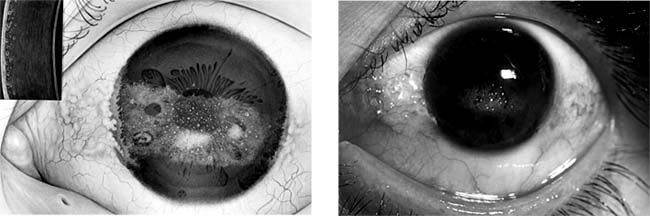

Climatic Droplet Keratopathy (Labrador Keratopathy, Spheroid Degeneration of the Cornea) (new window  Figure 6-13)

Climatic droplet keratopathy affects mainly men who work out of doors. The corneal degeneration is thought to be caused by exposure to ultraviolet light and is characterized in the early stages by fine subepithelial yellow droplets in the peripheral cornea. As the disease advances, the droplets become central, with subsequent corneal clouding causing blurred vision. Treatment in advanced cases is by corneal transplantation.

Figure 6-13

Figure 6-13: Two photos showing climatic droplet (Labrador) keratodystrophy. Inset at left shows slitlamp view. (Photo at left courtesy of A Ahmad.)